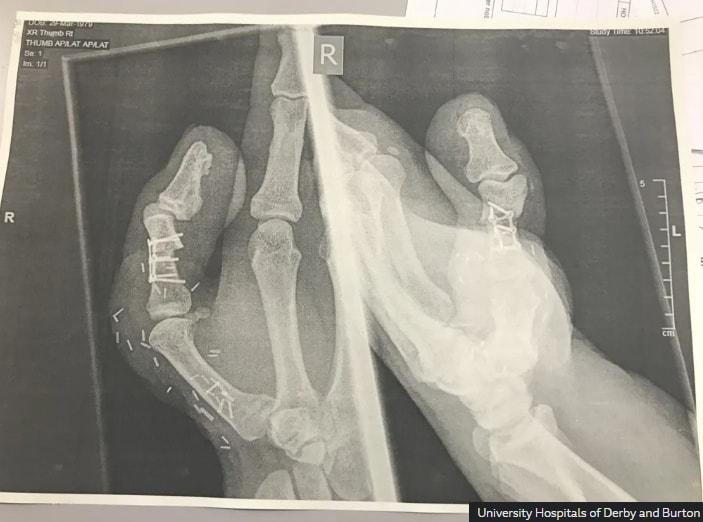

엄지손가락 절단당하자 발가락 붙인 구두 수선공…"일 계속하기 위해"